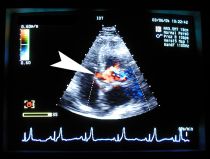

Farb-Dopplersonographie

Farb-Dopplermessungen helfen uns, Vorhofseptum-Defekte, Ventrikelseptum-Defekte, Ductus arteriosus botalli und andere angeborene Herzerkrankungen genauer zu diagnostizieren. Insbesondere kleine Herzscheidewandlöcher zwischen den Vorhöfen oder zwischen den Hauptkammern lassen sich sonst kaum diagnostizieren. Zusätzlich nutzen wir den Farb-Doppler bei Mitral- und Trikuspidalinsuffizienzen, um die genaue Ausbreitung des Refluxes über die ganze Ausdehnung der Vorhöfe zu bestimmen.